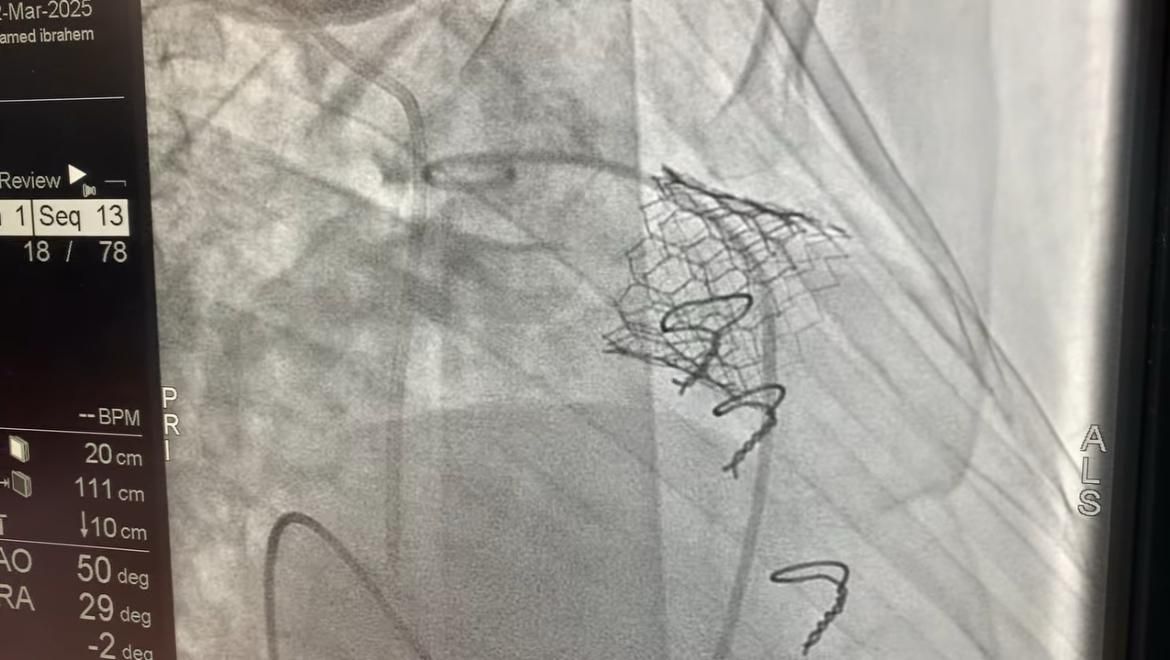

الأحد، 23 مارس 2025 04:12 مأعلنت وزارة الصحة والسكان، نجاح المعهد القومي للقلب التابع للهيئة العامة للمستشفيات والمعاهد التعليمية، في إجراء 4 عمليات زراعة صمام رئوي بالقسطرة التداخلية، باستخدام صمام (MYVAL)، بتكلفة تقدر بمليون جنيه للعملية الواحدة، وذلك ضمن الجهود المستمرة لتقديم أحدث العلاجات لمرضى القلب بأعلى معايير الجودة.

ومن جانبه، قال الدكتور محمد مصطفى عبدالغفار رئيس الهيئة العامة للمستشفيات والمعاهد التعليمية، أن زراعة الصمام الرئوي بالقسطرة تقنية حديثة تُمثل بديلًا آمنًا لجراحة القلب المفتوح، حيث يتم إدخال الصمام الجديد عبر قسطرة دون الحاجة إلى شق الصدر أو إيقاف القلب، مما يقلل بشكل كبير من المخاطر والمضاعفات.

واستكمل أن هذه التقنية تتيح تقليل فترة التعافي، بحيث يغادر المرضى المستشفى في غضون 24 إلى 48 ساعة فقط، بالإضافة إلى تجنب مخاطر الجراحة، مثل النزيف الحاد والعدوى وفترات النقاهة الطويلة، مما يؤدي إلى تحسين جودة الحياة للمرضى الذين يحتاجون إلى استبدال الصمام بعد جراحات القلب السابقة.